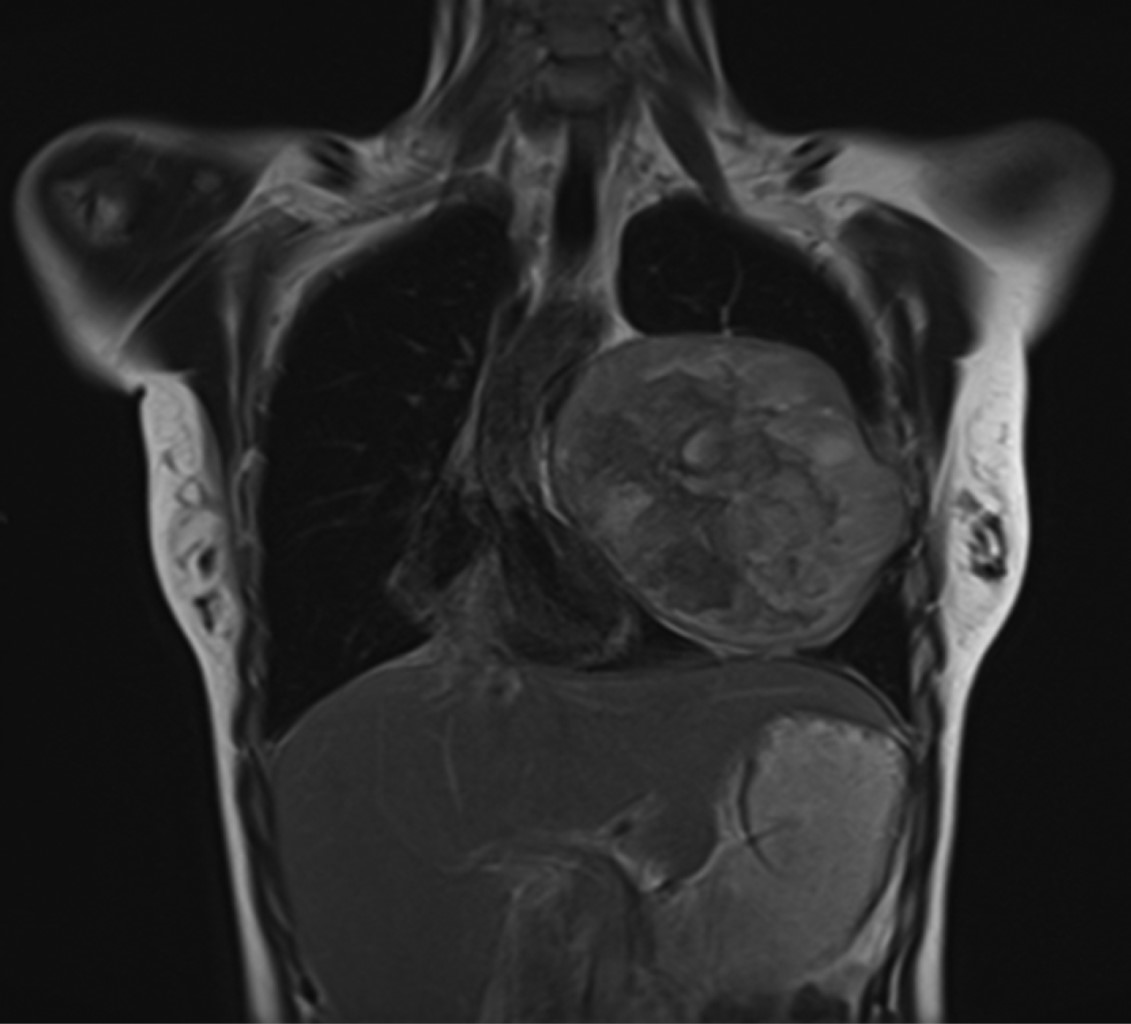

A su valoración se encontró alerta, orientada, con signos vitales con SpO2 95% al aire ambiente, TA 95/63 mmHg, FC 86 lpm. A su ingreso se solicitaron estudios preoperatorios, los cuales se encontraron dentro de parámetros normales. De igual manera, se solicitó electrocardiograma, el cual se encontró sin alteraciones. Se realizó TC de tórax que reportó lesión ocupante en el lóbulo inferior del pulmón izquierdo de aproximadamente 11.43 × 12.06 cm (Figuras 1 y 2), así como ecocardiografía que encontró derrame pericárdico moderado, engrosamiento de ventrículo izquierdo y FEVI 60%.

Figura 1

Figura 2